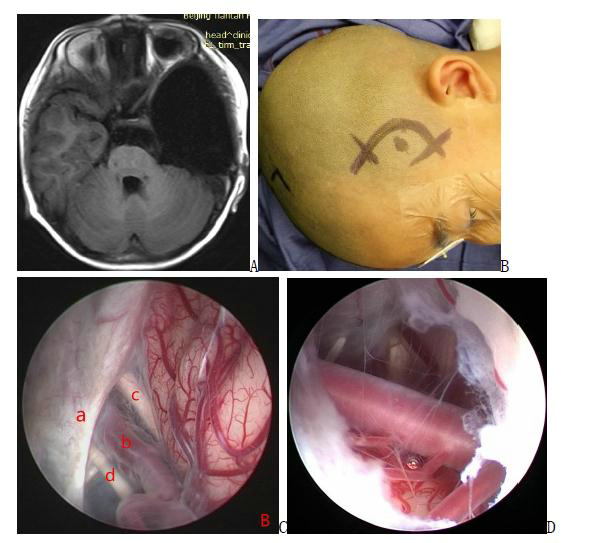

Figure 5. A preoperative magnetic resonance image; B intraoperative screenshot, endoscopically visible periventricular foramen structures; C, D base of the three ventricles and fistula (basilar artery visible below the fistula)

Figure 6. a pre-surgical MRI image; b illustration of scalp incision; c intraoperative screenshot, endoscopic view of 3 alternative fistula sites between the cyst and the basal pool: between the moto neurotic nerve and the cerebellar curtain margin; between the moto neurotic nerve and the internal carotid artery; and between the internal carotid artery and the optic nerve; d the basilar artery is visible below after fistula. a: cerebellar curtain b: internal carotid artery c: optic nerve d: moto neurotic nerve